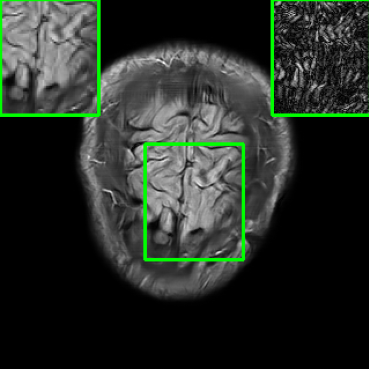

| Ground Truth | Vanilla MoDL | RS-E2E | SMUG |

![]() |

| PSNR = dB | PSNR = 21.48 dB | PSNR = 23.09 dB | PSNR = 26.51 dB |

| AT | Score-MRI | Deep-Equilibrium | Weighted-SMUG |

| PSNR = 26.34 dB | PSNR = 25.78 dB | PSNR = 21.32 dB | PSNR = 26.89 dB |

Results for the FastMRI Knee Dataset: In Fig 5 and Fig 7, we report PSNR and SSIM results of different methods at two sampling acceleration factors for the knee dataset. Therein, we observe quite similar outcomes to those reported in Fig 3. Figs. 6 and 8 show reconstructed images by different methods for knee scans at 4x and 8x undersampling, respectively. We observe that SMUG and Weighted SMUG show fewer artifacts, sharper features, and fewer errors when compared to Vanilla MoDL and other baselines in the presence of the worst-case perturbations.